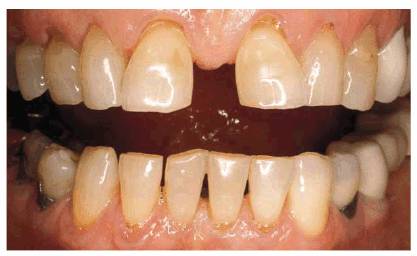

TREATMENT: The teeth were slightly reproportioned by stripping and

disking the distal surfaces of the central and lateral incisors (see Figure 23-10B). The key to successful restorative

diastema closure is creating the illusion of a believable "natural"

tooth width in the central and lateral incisors. Figure 23-10C shows a narrower width of the

central incisors after the distal surfaces have been sufficiently reduced and

ready for full-veneer bonding to close the central incisor diastema and restore

the cervical defects. Final restoration is seen in Figure 23-10D

Figure 23-10B: Stripping and disking of the distal surfaces of the central and lateral incisors were done to slightly reproportion the teeth.

Figure 23-10C: The narrower width of the central incisors readies the diastema for closure.

Figure 23-10D: The final full-veneer bonding closed the diastema and restored the cervical defects.

RESULT: Figure 23-10F shows an entirely new smile with

better proportioned teeth rather than two oversized teeth. Note that the

cervical erosion on the maxillary right side has been simultaneously restored

with composite resin bonding. The mandibular anterior incisors were also

cosmetically contoured to give them a level plane of occlusion. Comparing the

before and after smiles (see Figures 23-10E

and F)

specifically illustrates how the patient's mid-upper lip naturally drops rather

low, forming a "cupid's bow." This lowered lip line tends to mask the

extra width of the central incisors, which also contributes to the illusion.

Figure 23-10E and F: Comparison of the before and after smiles shows an entirely new smile that is better proportioned by treating four anterior teeth. If only the two central incisors had been bonded, two oversized central incisors would have resulted.